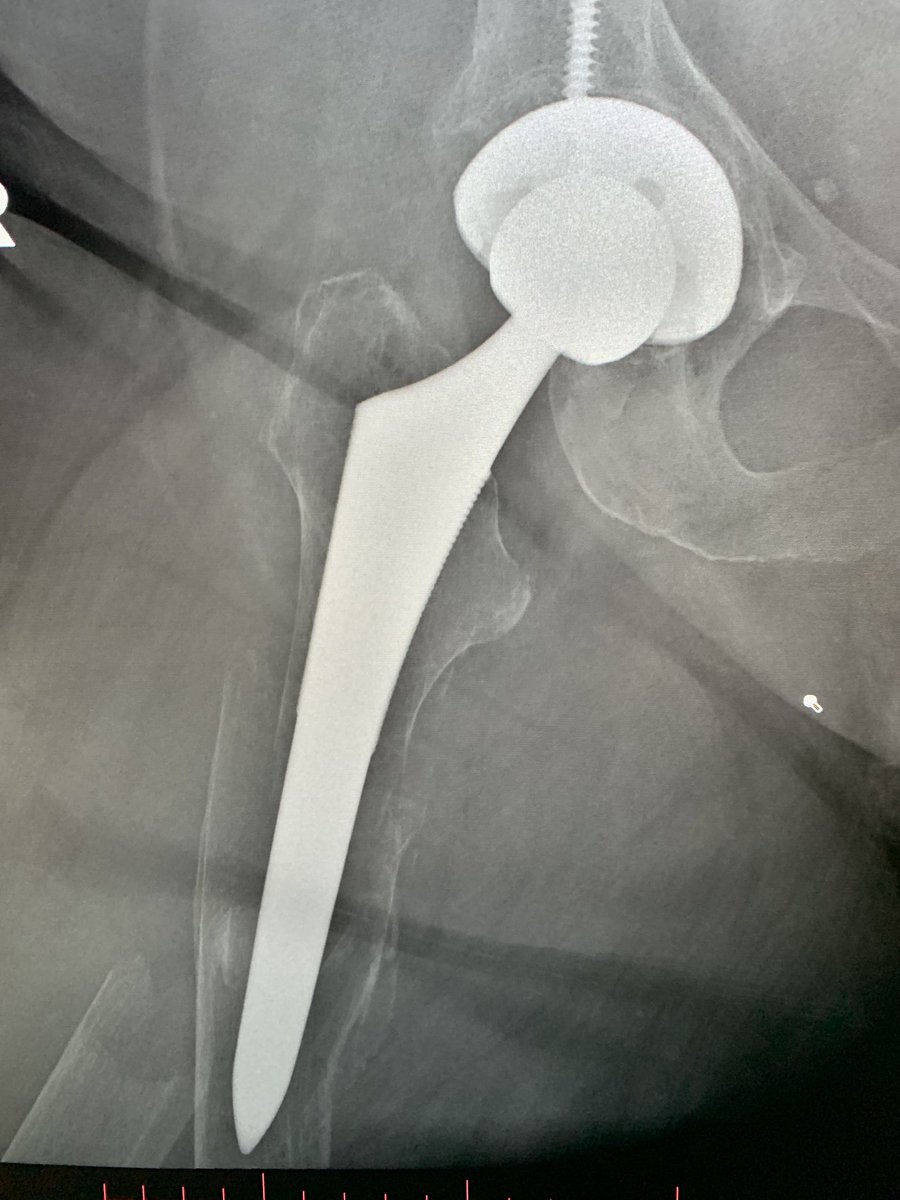

From twitter.com

RJ on Twitter "Is it considered any standard of care to give this old Cementless Hip Replacement Recovery Time Cementless fixation in primary total hip arthroplasty (tha) has increased worldwide and is currently the primary choice of fixation in the united states; The aim of the study was to investigate functional outcome and quality of life 4 weeks and 12 months after cementless total. “on average, hip replacement recovery can take around two to four weeks, but everyone is. Cementless Hip Replacement Recovery Time.